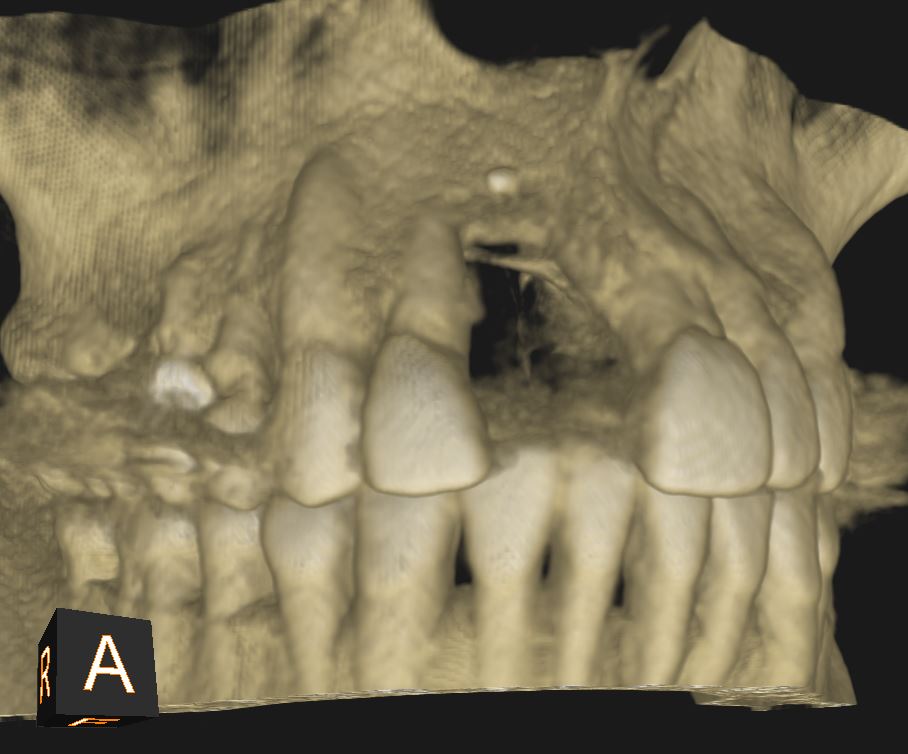

Greffe osseuse: Dans certains cas, la quantité d’os disponible dans la mâchoire n’est pas suffisante pour poser un implant de manière stable et durable. Pour recréer un volume adapté, différentes chirurgies pré-implantaires peuvent être proposées :

La greffe d’apposition (horizontale ou verticale) : cette technique consiste à ajouter de l’os pour élargir ou rehausser la mâchoire. Elle permet d’obtenir une base osseuse solide et adaptée à la pose de l’implant.

Le sinus lift (accès par voie latérale) : lorsqu’il manque de l’os en arrière du maxillaire supérieur, on accède au sinus par une paroi latérale et on le comble avec nos matériaux. Cela augmente la hauteur osseuse disponible.